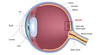

diabetic retinopathy

damage to the retina and iris caused by diabetes which can lead to blindness

is associated with several complications (cataract, glaucoma, acute hyperglycaemia)

maculopathy

macula

surrounds the fovea - portion of retina with highest density of cones (colour and high resolution image)